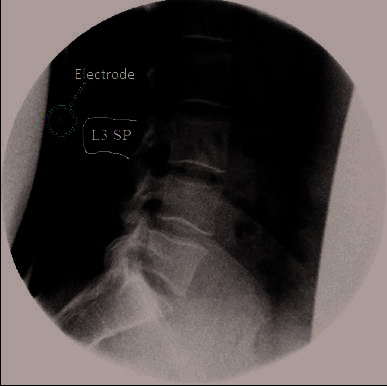

2.4电极定位准确性

电极应用精度 准确性依赖于骨性解剖结构的主观识别 标志点,因此现有方法受限于人为主观性和个体解剖结构差异[32–35]。然而有研究表明,当技术结 合时,准确性可显著提高[36]。本研究被整合到一项正在进行的更大规模的正常值数据库研究中,该 研究要求在开始负重成像之前先进行仰卧位QF成像。为了提高电极定位准确性,在仰卧位操作过程 中将一个电极放置在L3棘突上。这为电极的应用提供了更优的解剖学参考点(图3)。